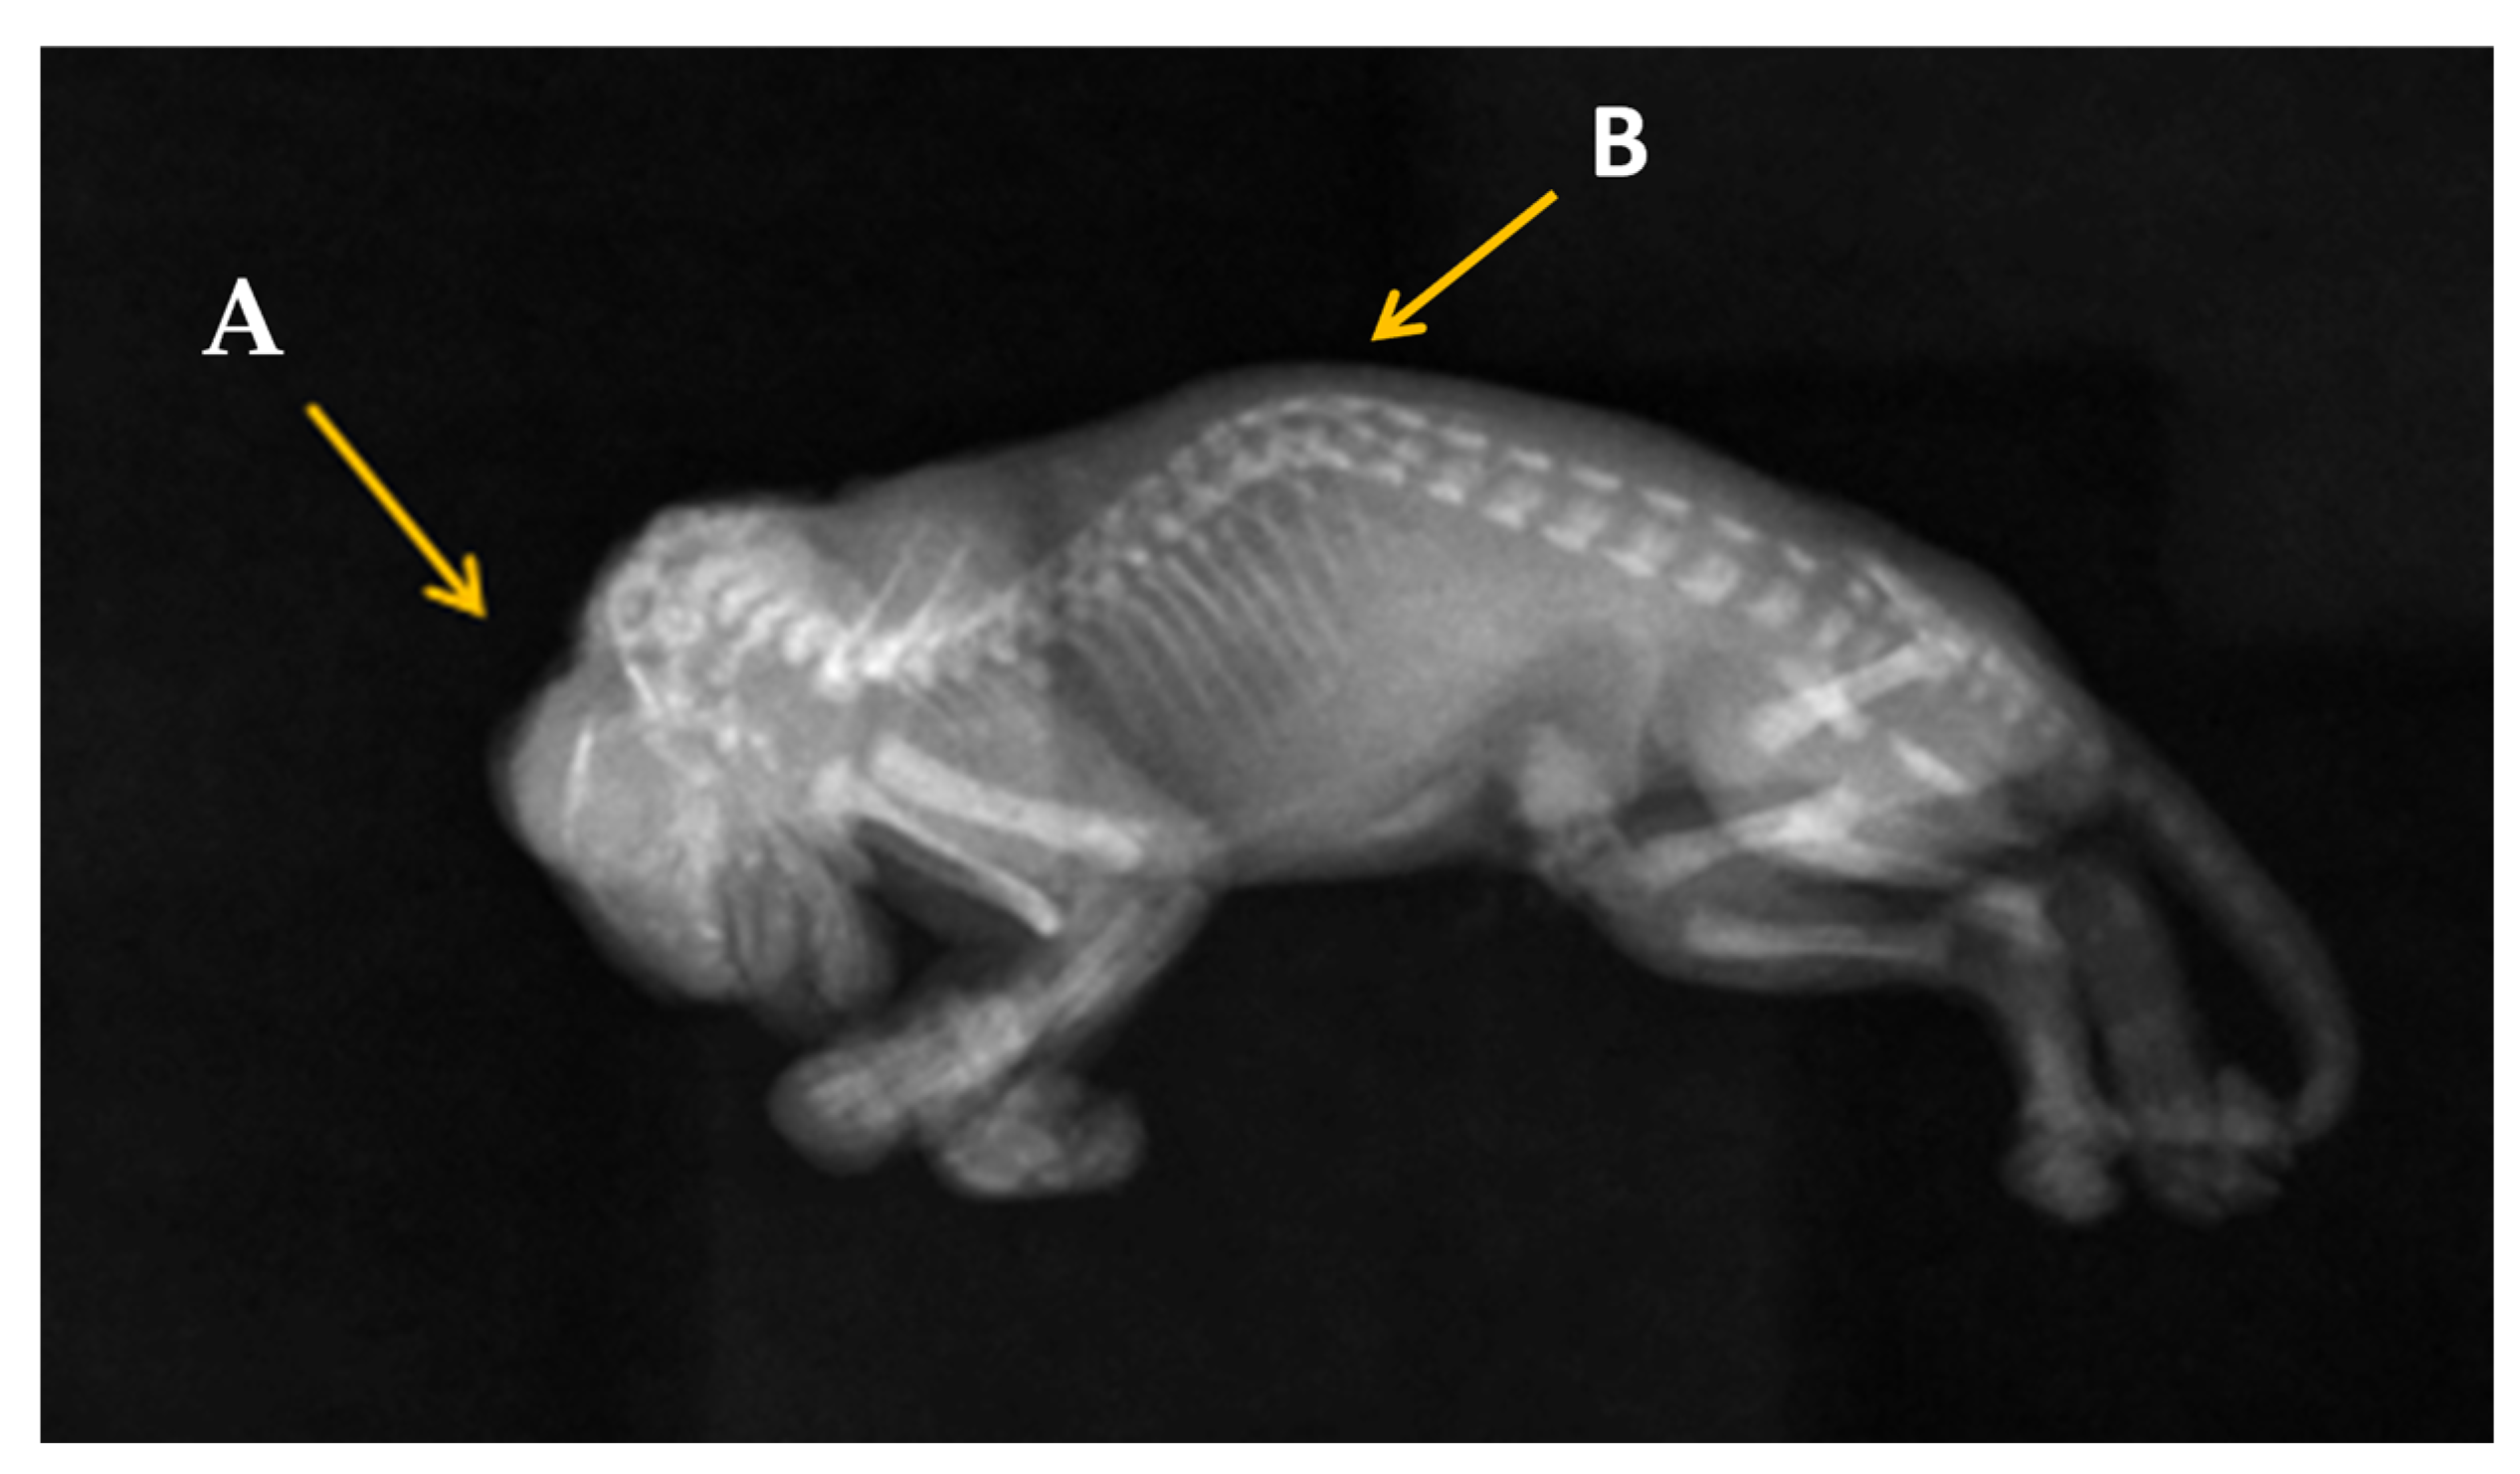

2.4. Radiography Investigation

3. Results

3.1. Clinical Presentation